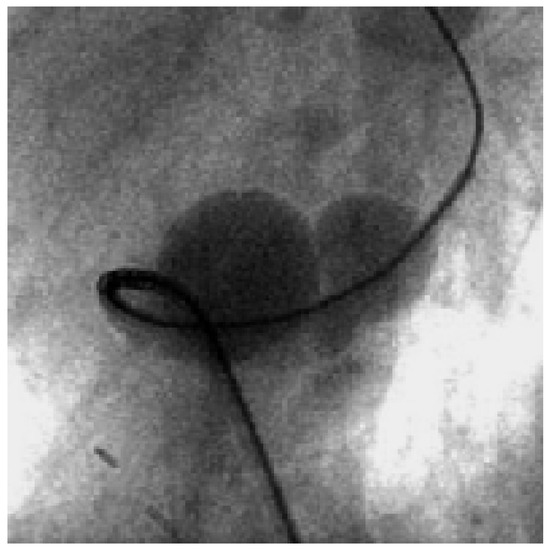

Traumatic Tamponade and Ventricular Septal Defect

A 30-year-old man sustained a knife wound in the 9th left intercostal space when he was involved in a fight as a bodyguard in a night club [...] Full article

Figure 1